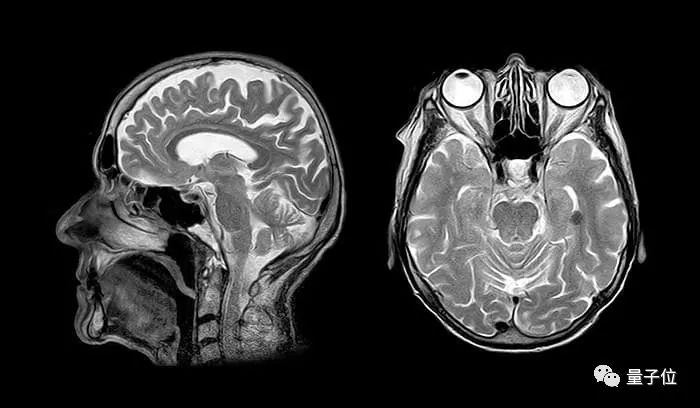

在美国,有将近五百万人拥有医学影像相关数据。这些数据包括 CT ,核磁共振和X光片等相关图像及诊断报告。

除此之外,这些影像往往附带患者的个人信息,以及就诊医生、医院、病史等诊疗流信息。这些信息不但涉及隐私,还事关患者的生命安全。因此,这些信息需要严密的保护。

医学影像是指为了医疗或医学研究,对人体或人体某部分,以非侵入方式取得内部组织影像的技术与处理过程,是一种逆问题的推论演算,即成因(活体组织的特性)是经由结果(观测影像信号)反推而来。